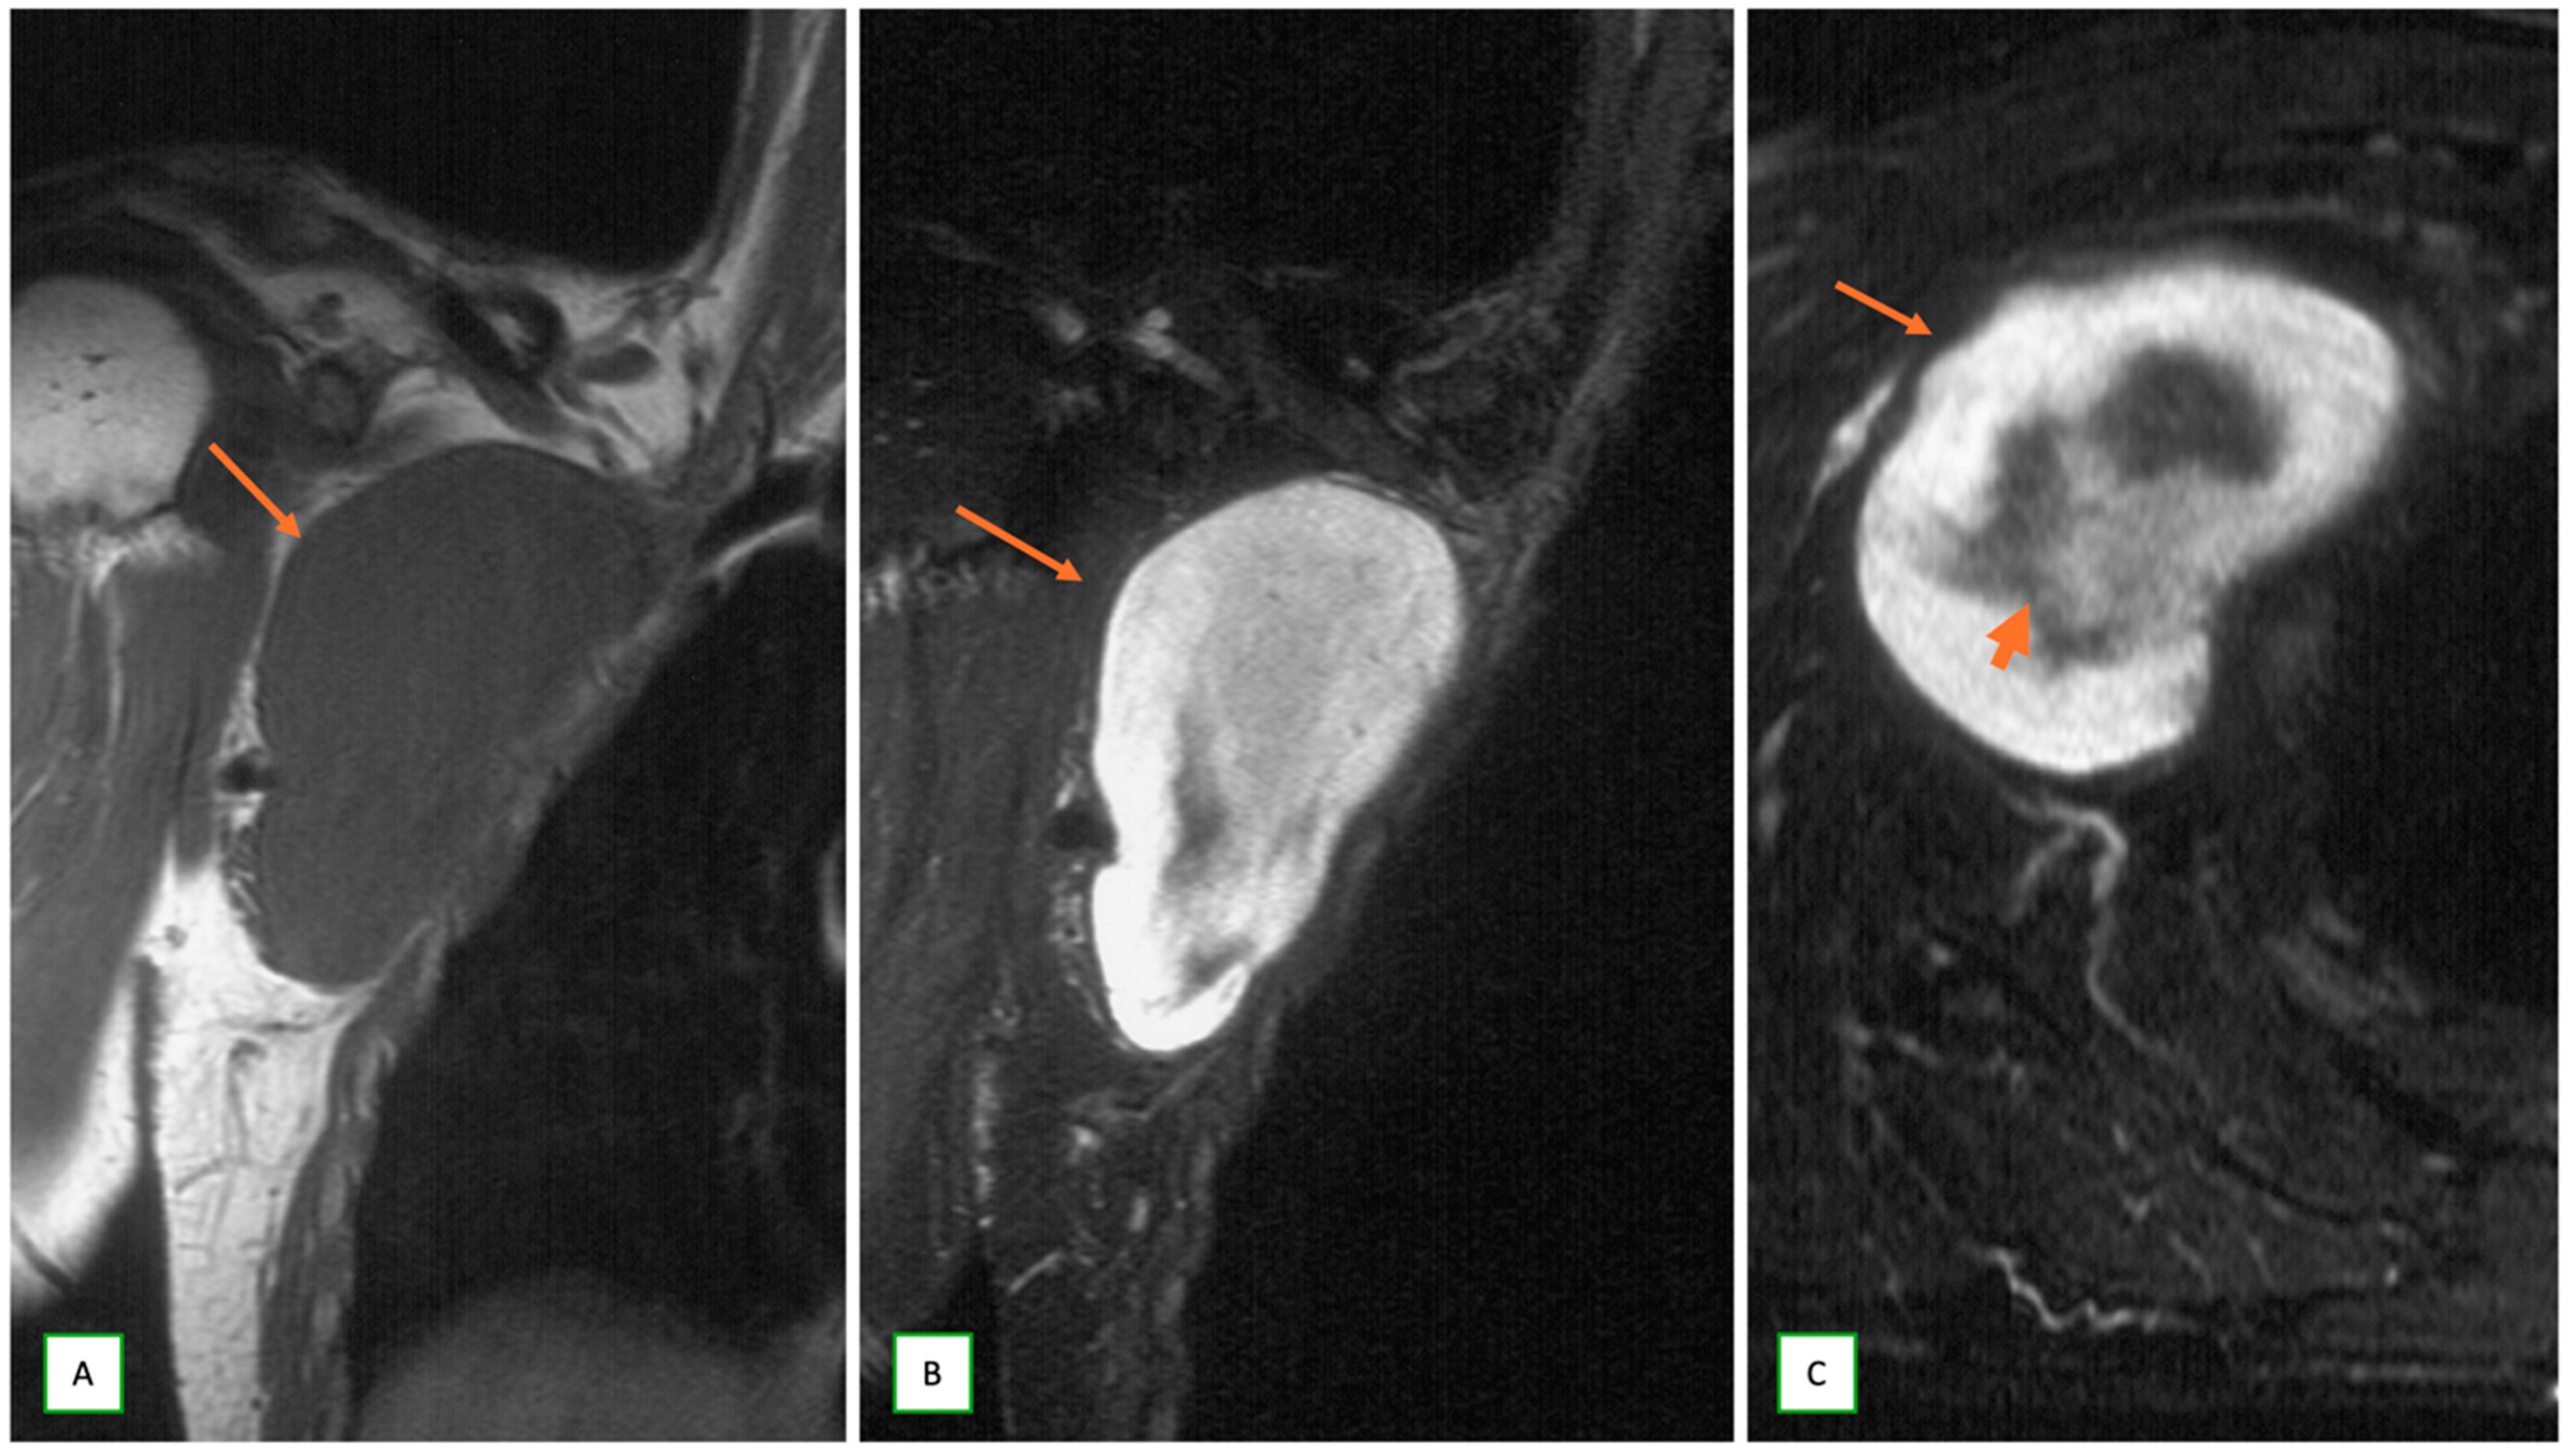

- Primary Sarcomas: Soft-tissue sarcomas are uncommon, accounting for just over 1% of adult malignancies. Synovial sarcoma, clear cell sarcoma, and epithelioid sarcomas are known to involve peripheral nerves. CT/MR reveals a large soft tissue mass with areas of necrosis or calcification and heterogeneous contrast enhancement. F-18 FDG uptake is useful for both tumor staging and treatment assessment (Figure 26, Figure 27 and Figure 28).